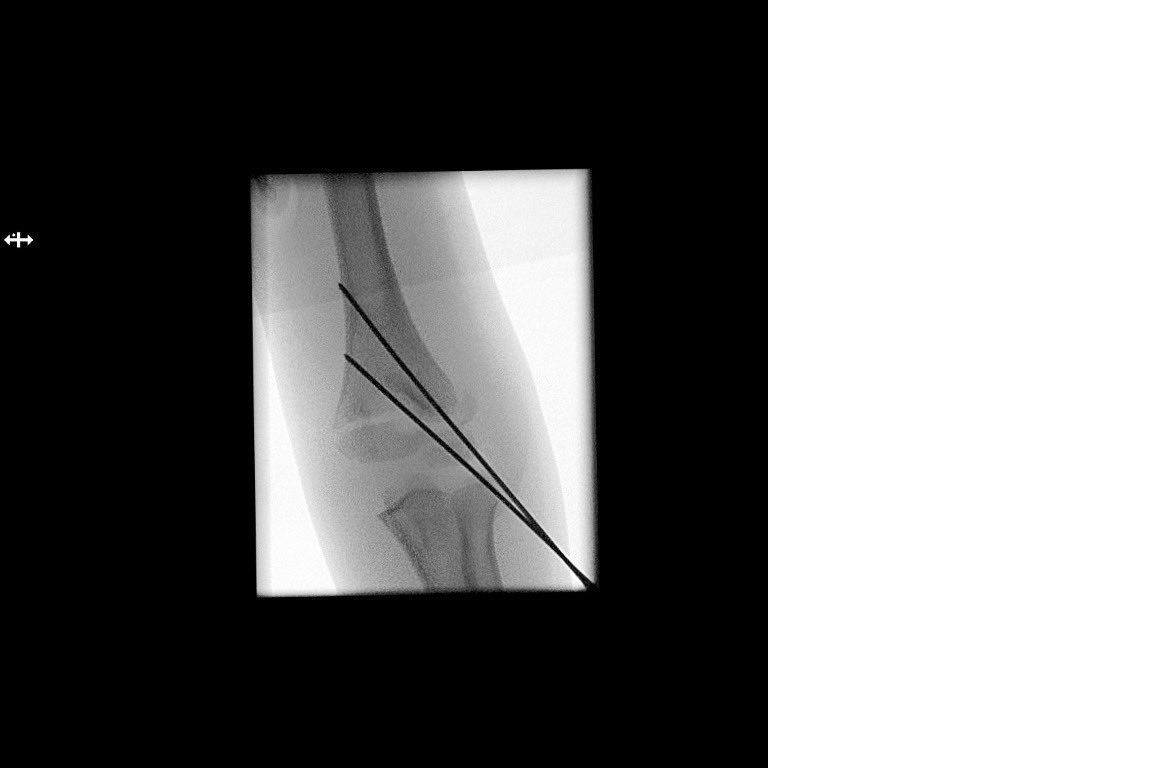

A little, flexible K-wire can do the trick! #Kapandji #BasicPhysics #LeverArm #PerCutaneousReduction #SupraCondylarFracture #MedTwitter #orthotwitter #OrthoTweetorial #SundayThoughts